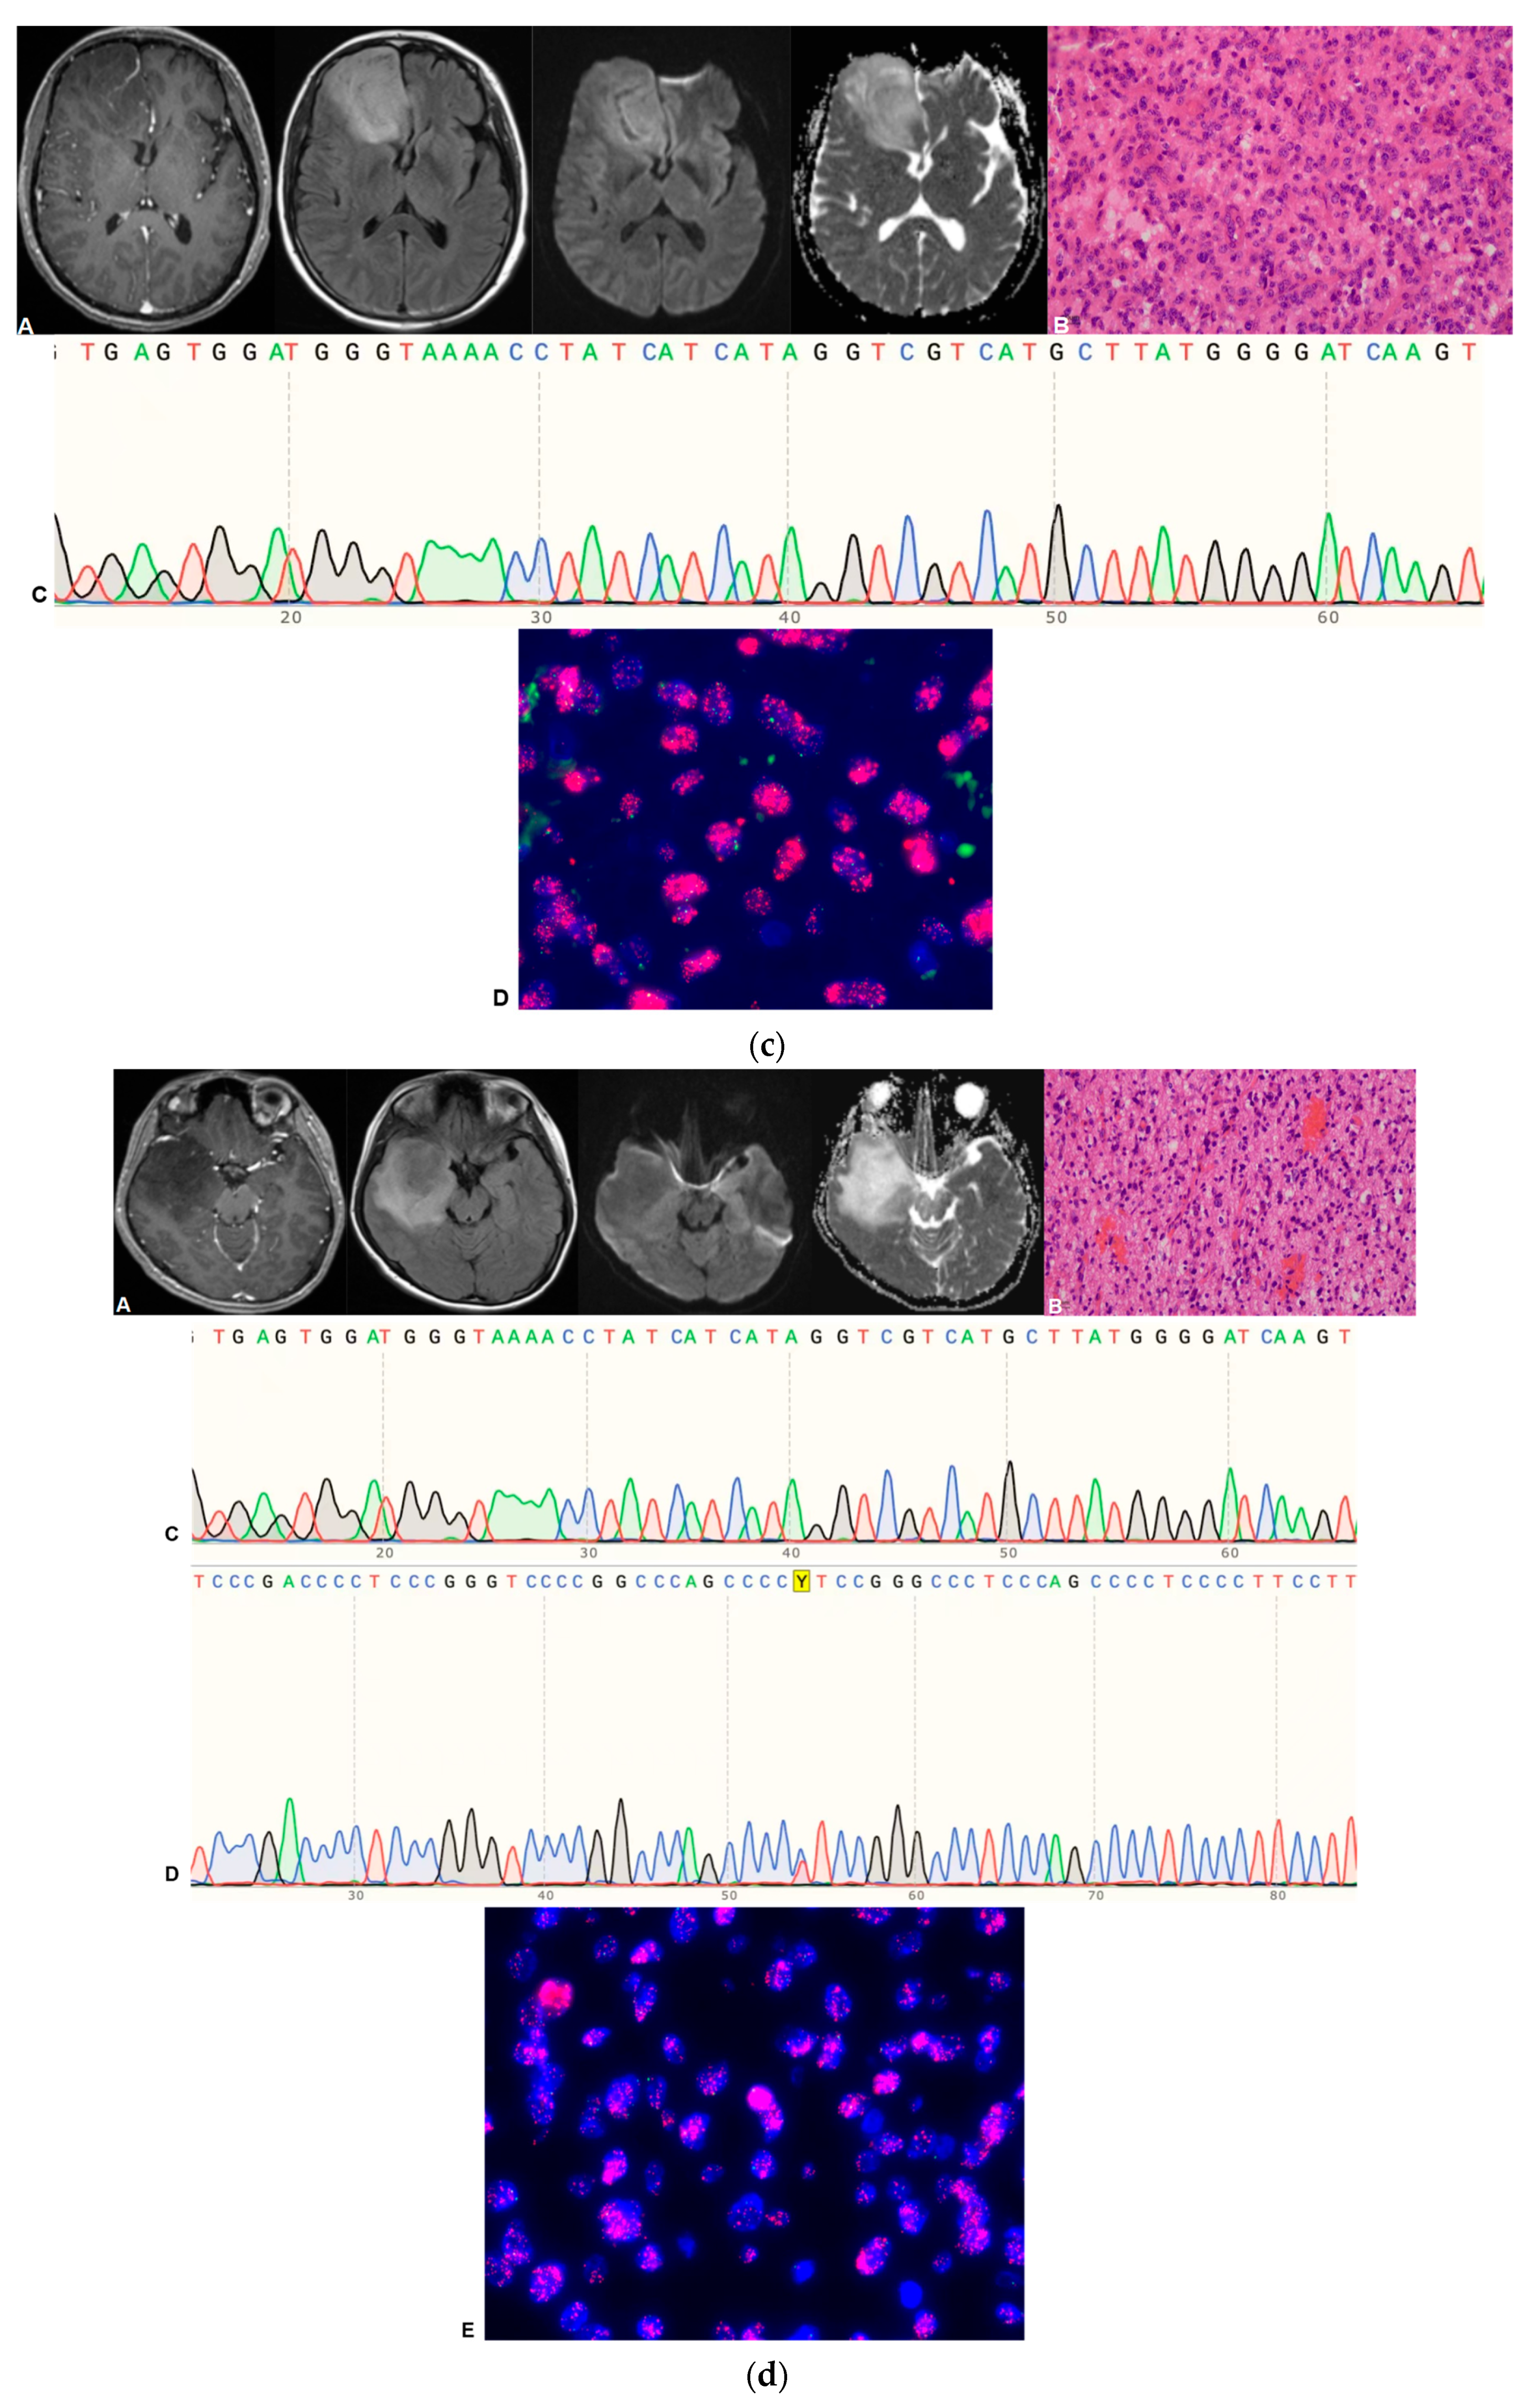

4. Pathological Grading and Molecular Diagnosis